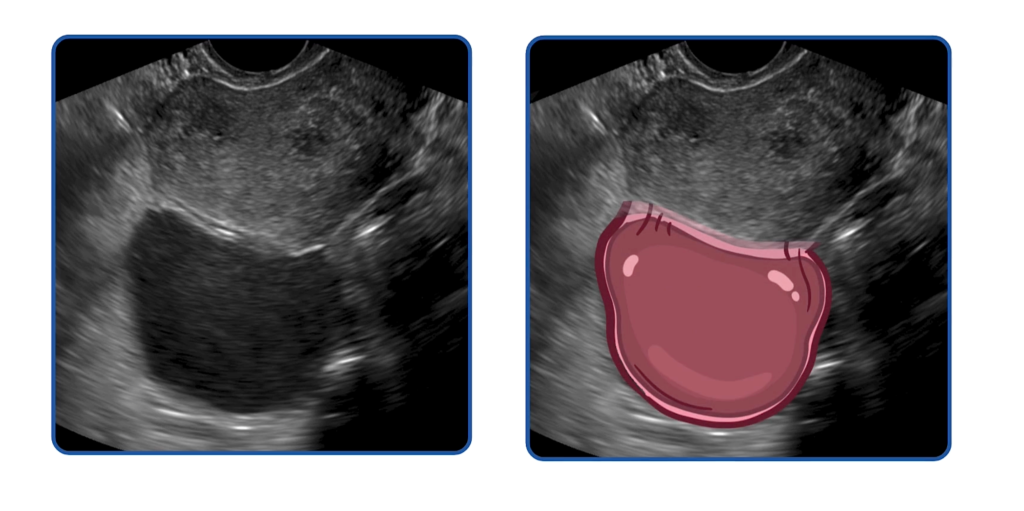

好,我们回到诊断部分。超声检查可以增强你对子宫内膜异位症的怀疑,同时也有助于排除其他导致慢性盆腔疼痛或不孕的原因。典型的超声表现包括盆腔或附件区肿块,如卵巢子宫内膜异位囊肿或深部浸润型子宫内膜异位症。内膜异位囊肿通常表现为内部回声均一、低强度的囊性病变,与陈旧性积血相符。

需要注意的是,在某些情况下,超声检查可能无法发现明显的结构异常。事实上,在绝大多数情况下,超声检查是正常的。但这并不能排除子宫内膜异位症的可能性。超声的作用主要是用于识别可能的其他盆腔疼痛原因,而不是依赖某一个特异性的超声征象来确诊子宫内膜异位症。